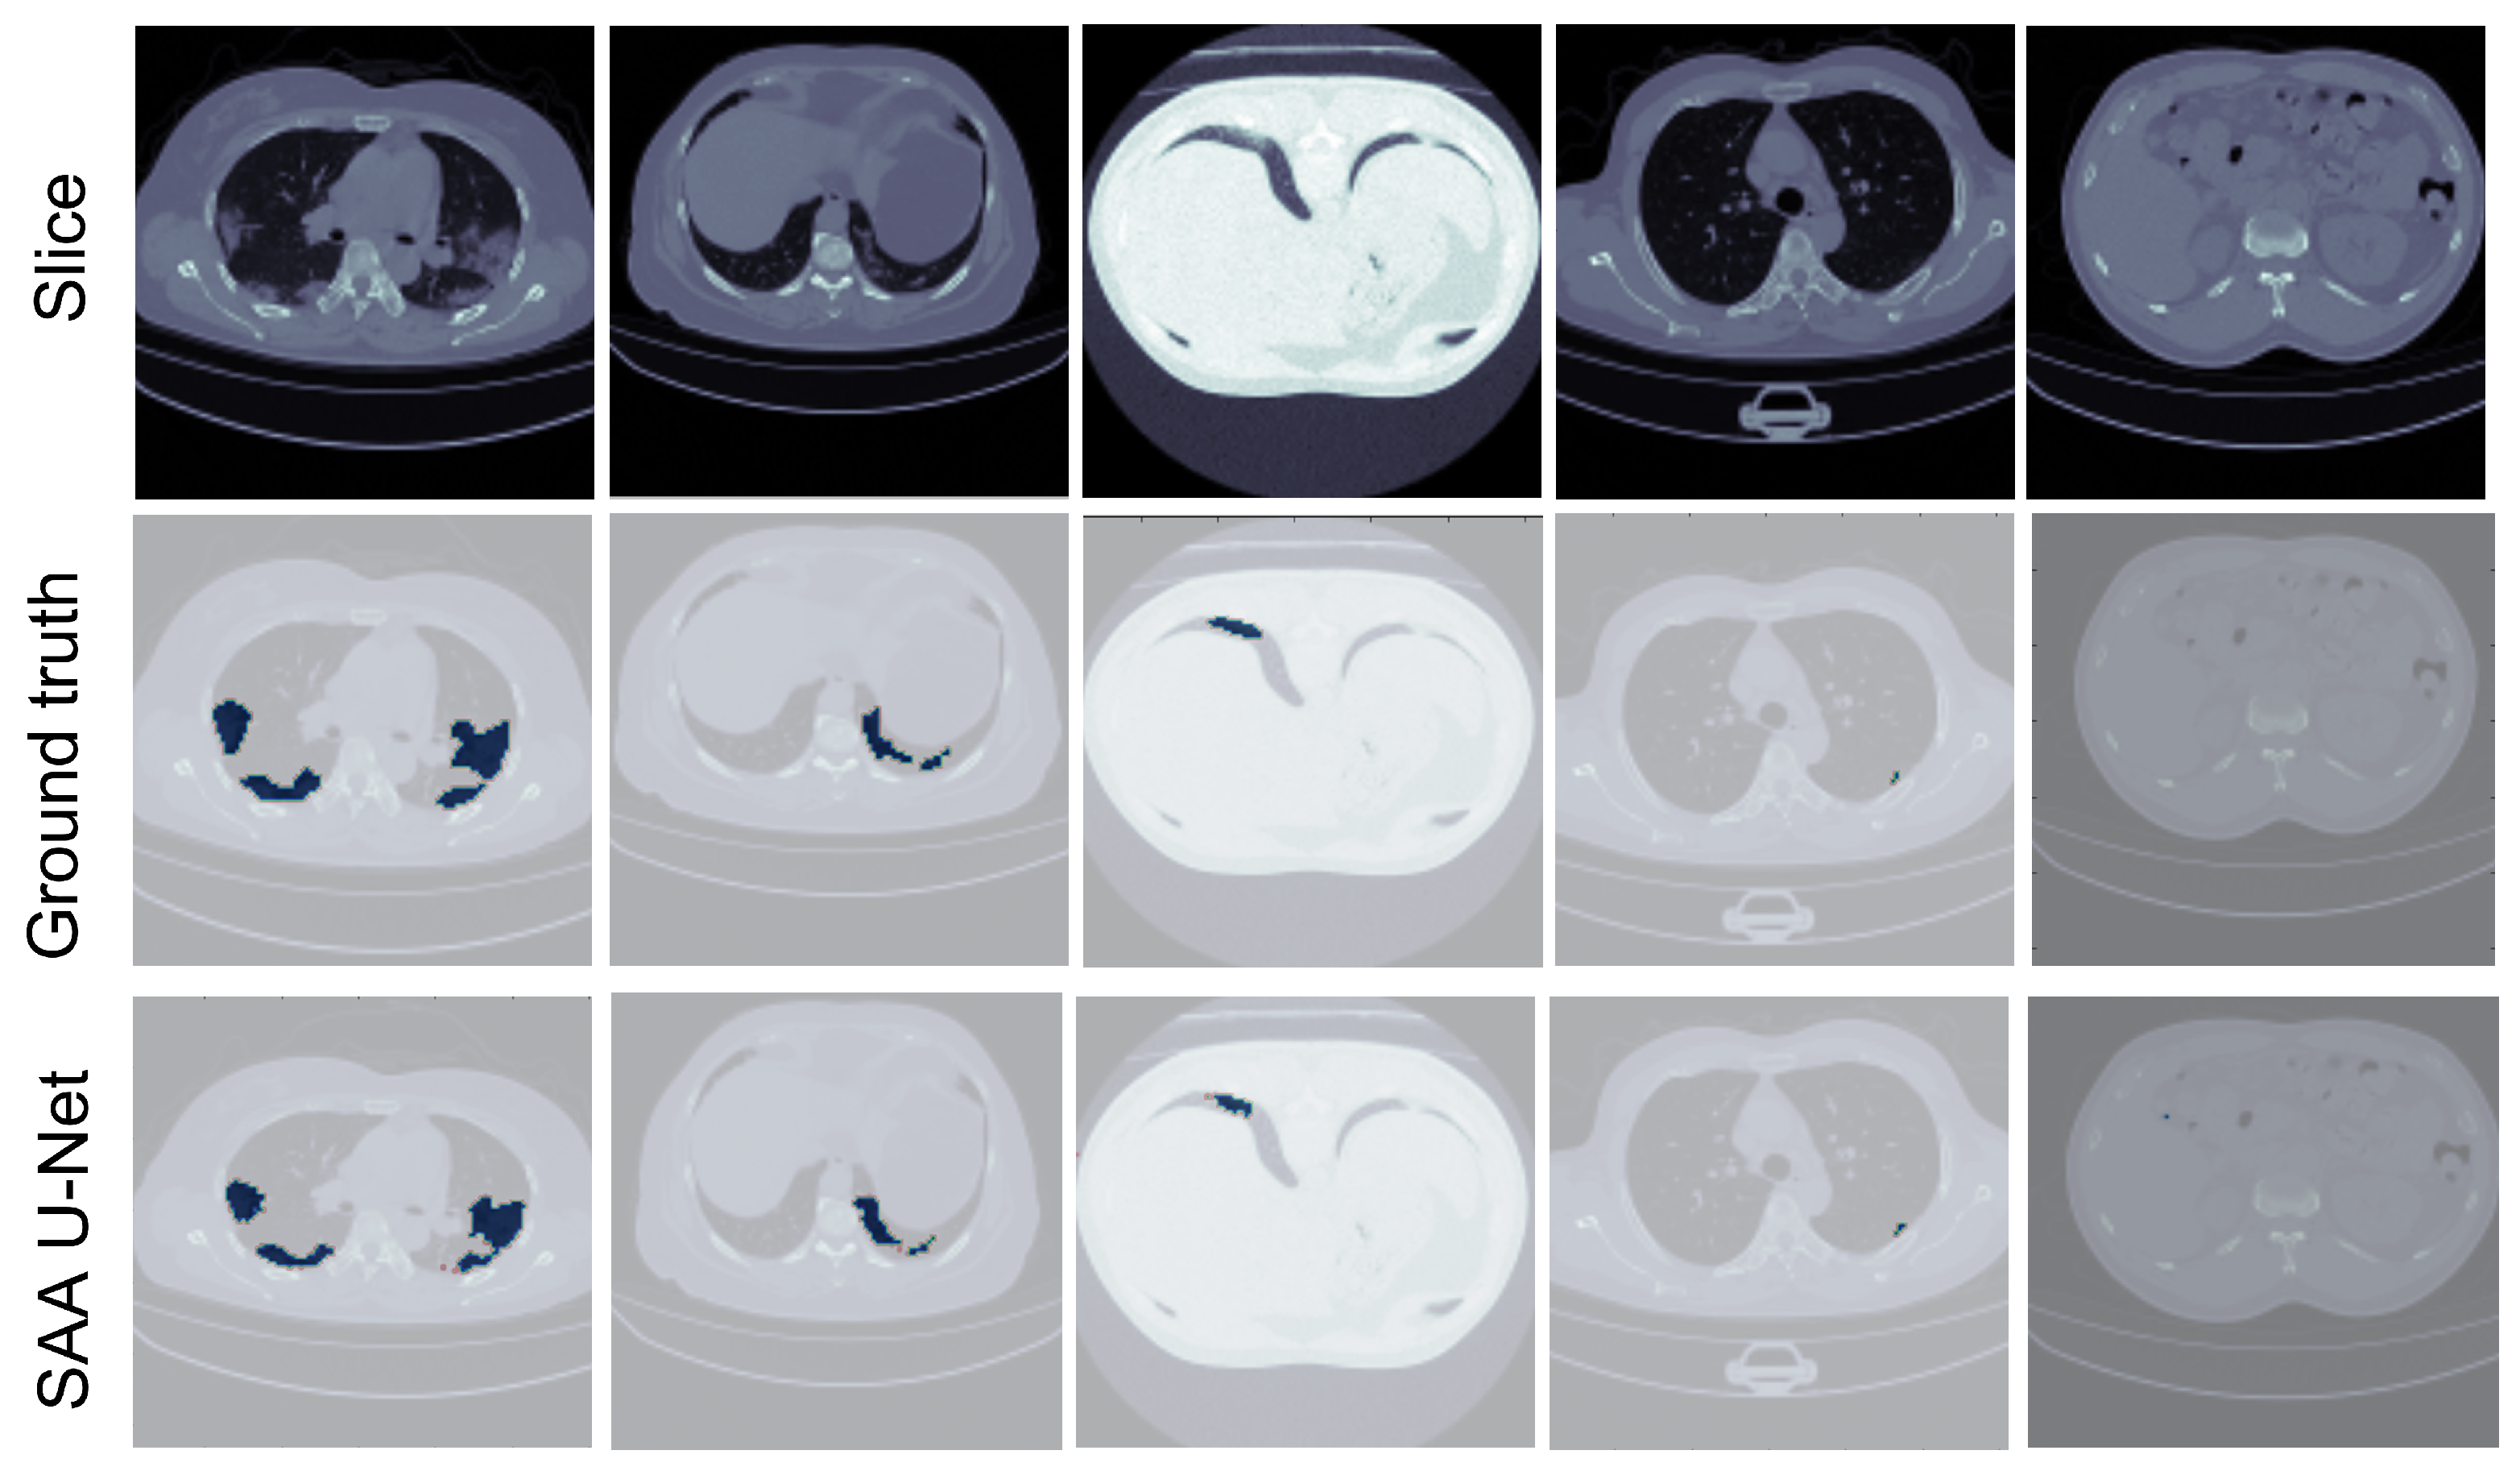

7. Discussion